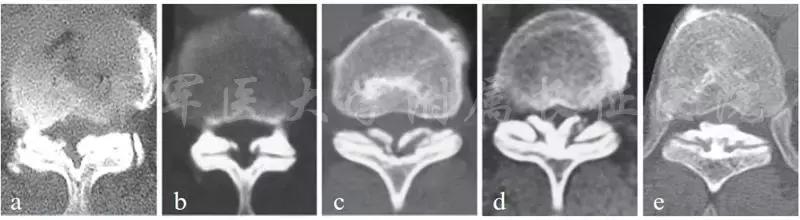

1920年Polar教授通过X线第一次诊断并命名了胸椎黄韧带,之后,胸椎黄韧带逐渐成为胸椎脊髓压迫的主要原因之一[1]。同后纵韧带骨化一样,胸椎黄韧带骨化主要发生在亚洲人群。据报道,日本整体发病率约36%,亚洲南部地区发病率为3.8%[2-4]。从解剖学角度看,胸椎黄韧带主要由内侧的椎板部分和两侧的囊部分组成。通常情况下骨化开始形成于囊部分,然后逐渐向中间和腹侧发展。最后双边骨化的黄韧带在椎板中部融合增厚形成巨大块状骨化物。因此根据CT上骨化黄韧带发展的过程,Sato T等将骨化黄韧带分为五种类型[5](图1):

1.侧块型:骨化仅局限于黄韧带囊性部分;

2.延伸性:骨化向韧带中间部发展,但仍然较薄;

3.扩大型:骨化物宽度与延伸型相似,但是厚度增加,造成椎管后正中部狭窄;

4.融合型:骨化位置类似扩大型,但是双边骨化病变在中部融合;

5.结节型:双边骨化块在中间融合增厚,呈结节状凸向椎管。

图1 胸椎黄韧带骨化的影像学分型 a 侧块型;b 延伸型;c 扩大型;d 融合型;e 结节型 (摘自《Ossification of posterior longitudinal ligament》,第二版, K. Yonenobu;K. Nakamara等)